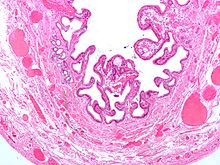

Холецистит (от греч. χολ — жёлчь и κστις — пузырь) — воспаление желчного пузыря.

Микроснимок жёлчного пузыря при холецистите.